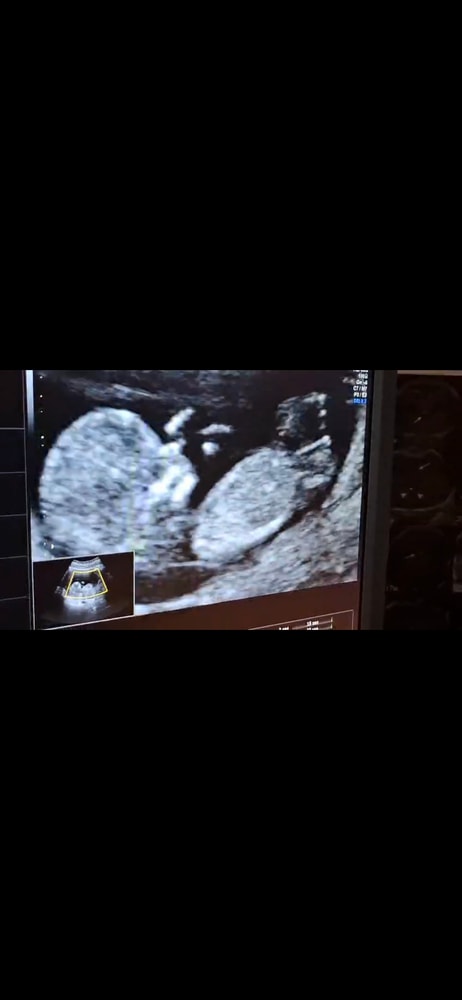

Мальчик или девочка?

Пол малышаСегодня был первый скрининг, знаю что пока рано говорить о том какой пол, но всё же интересно.

Кого вы видете?)

Vasilisa, девочка 90%) поверьте моему опыту, мальчики в 12 недель выглядят абсолютно по другому 😉😀